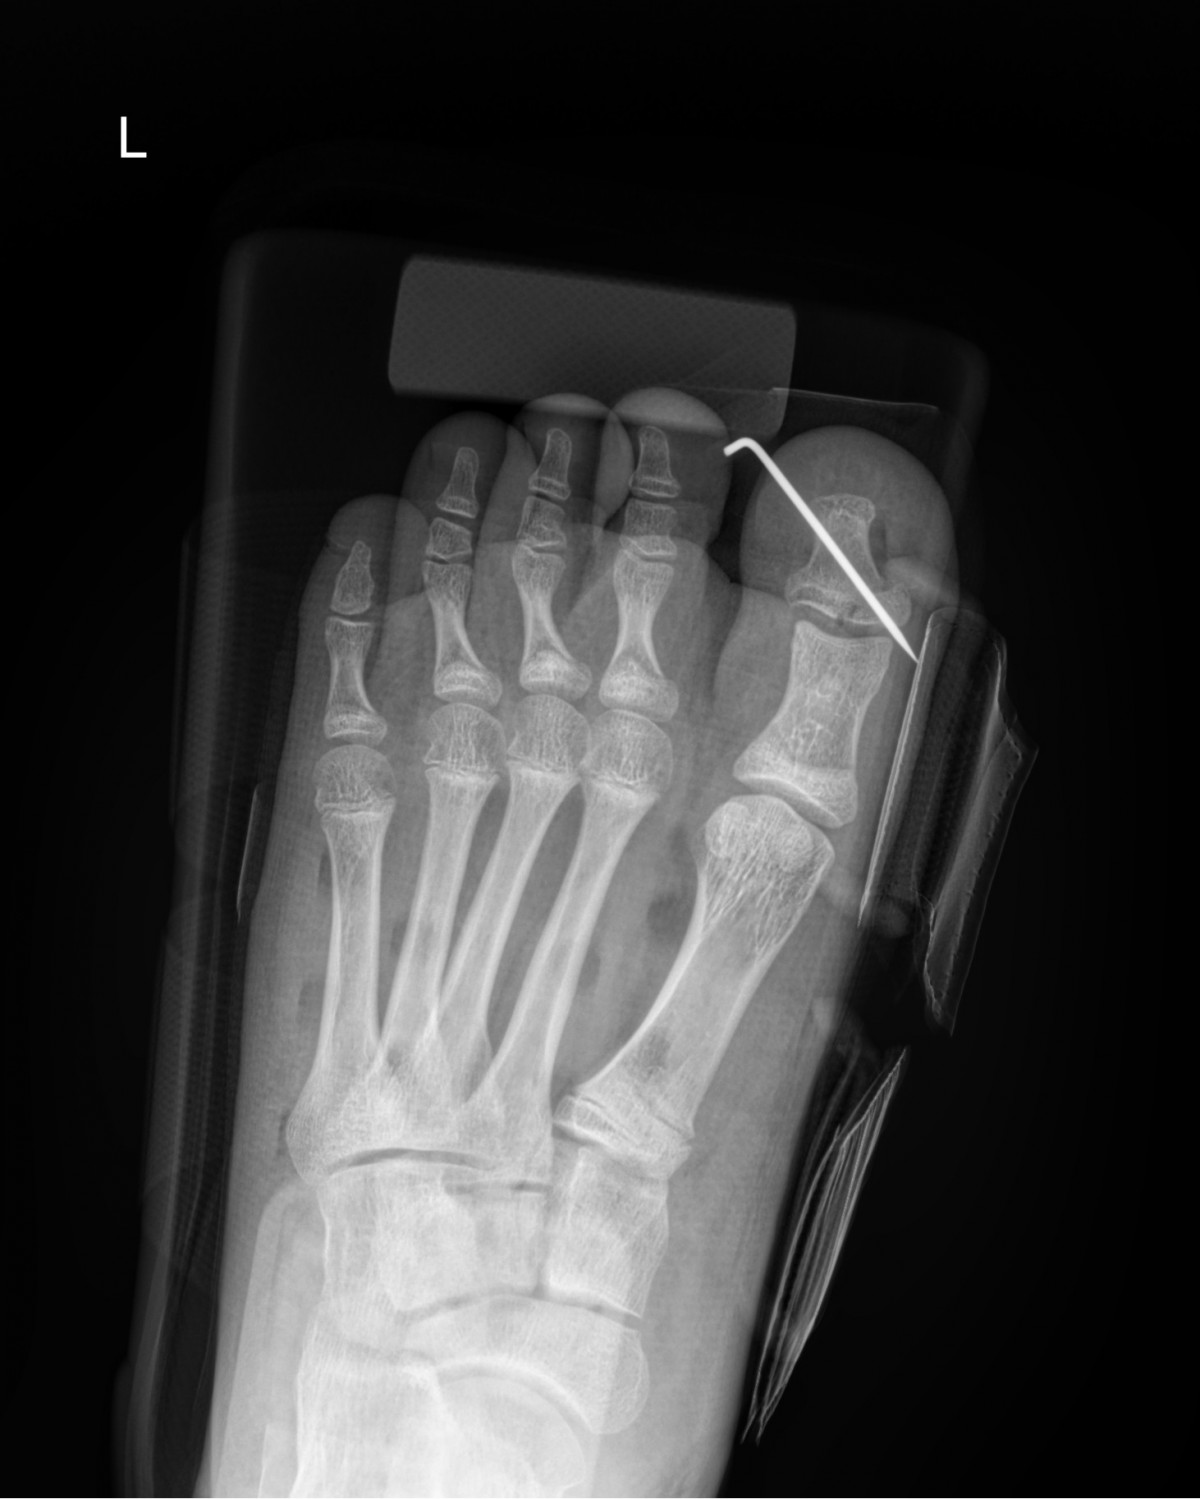

정지영원장님 발가락 골절 수술 김재O 환자

dae765e4d9ac96aee867c9d6292d8784_1758008899_6648.jpg